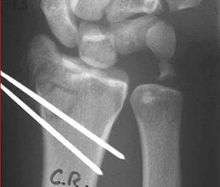

In displaced fractures, the fracture may be manipulated under anaesthesia and splinted in a position to minimize the risk of re-displacement. Typically, this involves injecting local anesthesia into the fracture (hematoma block) possibly combined with intravenous medication. A manual reduction is performed to reposition the displaced distal radius into its preinjury position and maintain this position in a well formed splint or cast.

Reduction

Closed management of a distal radius fracture involves first anesthetizing the affected area with a hematoma block, regional anesthesia, sedation or a general anesthetic.

Manipulation generally includes first placing the arm under traction and unlocking the fragments. The deformity is then reduced with appropriate closed manipulations (depending on the type of deformity) reduction, after which a splint or cast is placed and an X-ray is taken to ensure that the reduction was successful. The cast is usually maintained for about 6 weeks.

Closed treatment is frequently unsuccessful in maintaining a good position in adults, because there is frequently comminution of the fracture. Re-displacement and deformity can reoccur with an unacceptable ultimate result.